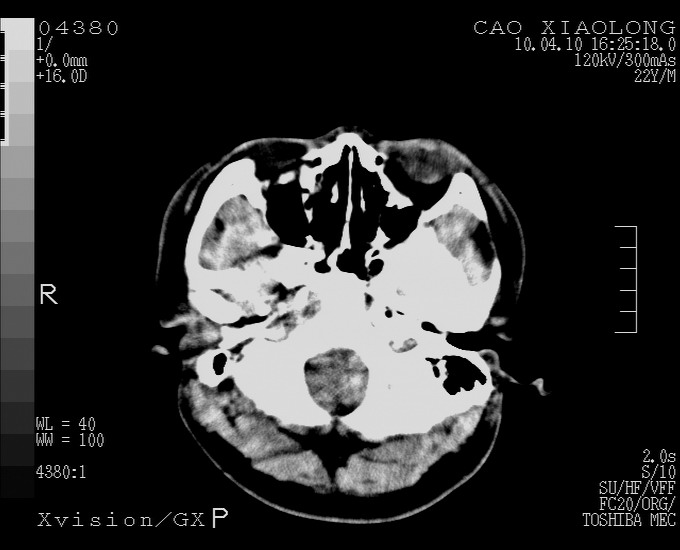

以下是引用随光逐影在2010-4-11 11:00:00的发言:[br]1)左侧额颞顶部硬膜下血肿。2)蛛网膜下腔出血。3)右侧颞顶部颅骨线形骨折。[br][br]20小时后复查:左侧额颞叶脑挫裂伤;左侧额颞顶部硬膜下血肿及蛛网膜下腔出血有吸收表现;右侧颞顶部颅骨线形骨折。[br]